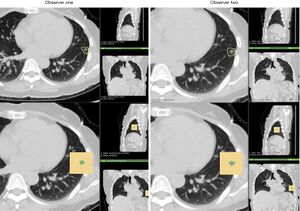

- 1.95 Imaging as Part of a Quality Assurance Program: Predictors of Interobserver Variability for Pretreatment Image Registration for Lung SBRT